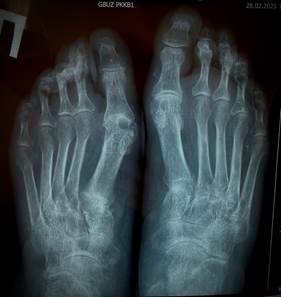

При лабораторном исследовании крови макроцитарная гиперхромная анемия с уровнем гемоглобина 83 г\л, лейкопения - 3.18 х 10 ⁹/л, повышение СОЭ - 24 мм\ч, СРБ - 12.83 мг\л. Концентрация в крови мочевины 2.58 ммоль\л, креатинина - 72.5 мкмоль\л, гамма-глутамилтрансферазы - 167.8 Ед\л, , мочевой кислоты - 625.8 мкмоль\л, щелочной фосфатазы - 140 Ед\л. Скорость клубочковой фильтрации - 92 мл\мин\1.73 м². Уровень ферритина был 111.31 нг\мл, витамина В12 - 141 пг\мл. Остальные биохимические показатели крови и общий анализ мочи без особенностей. Электрокардиографически – синусовый ритм с ЧСС 67 в минуту, изменения миокарда. Заключение ЭХО-КГ: полости сердца не расширены, уплотнены створки аортального и митрального клапана, легочная гипертензия 0-1 степени (31+5 мм.рт.ст.), глобальная сократимость левого желудочка хорошая. Ультразвуковое исследование органов брюшной полости и почек не выявило патологии. Рентгенография органов грудной полости без патологии. По данным рентгенографии коленных суставов выявлен двусторонний гонартроз II стадии, кистей – рентгенологические признаки артрита II стадии (Рис.2). На рентгенограмме стоп определялся выраженный остеопороз, суставные щели обоих плюсне-фаланговых сочленений равномерно сужены, уплотнены суставные поверхности, в проекции головок плюсневых костей – пробойники, что характерно для подагрического артрита слева II стадии, справа III-IV стадии (Рис.3). По данным авторов, умеренные рентгенологические изменения суставов возникают в среднем через 9 лет, а более значительные через 10-15 лет и более [5]. У наблюдаемой нами пациентки рентгенологические изменения были выявлены уже через 5 лет от начала заболевания.

/Sinenko.files/image009.jpg)

Рисунок 3. Изменения стоп: стрелками показан рентгенологический феномен, типичный для поздней подагры – симптом «пробойника»